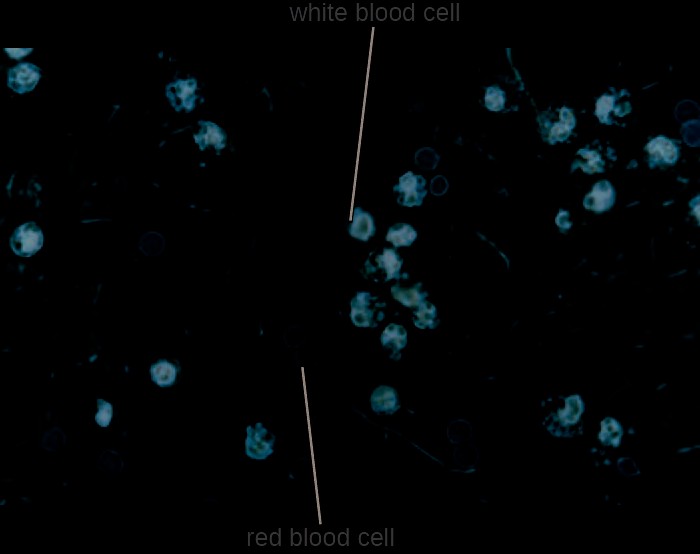

Stool samples, which should be processed promptly, are analyzed using serological or molecular techniques. One common method is to perform immunoassays for S. dysenteriae. (Other methods that can be used to identify Shigella include API test strips, Enterotube systems, or PCR testing. The presence of white blood cells and blood in fecal samples occurs in about 70% of patients[4] (Figure 24.17). Severe cases may require antibiotics such as ciprofloxacin and azithromycin, but these must be carefully prescribed because resistance is increasingly common.

Figure 24.17 Red and white blood cells can be seen in this micrograph of a stool sample from a patient with shigellosis.